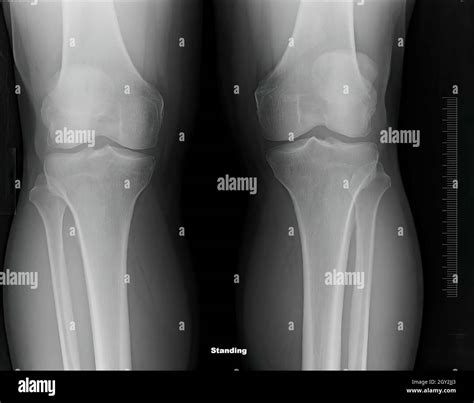

Healthy Knee Xrays

Knee pain is a common issue that affects people of all ages, from athletes to the elderly. Whether it's due to injury, arthritis, or other conditions, understanding the health of your knees is crucial for maintaining mobility and quality of life. One of the most effective ways to assess knee health is through Healthy Knee X-rays. These diagnostic tools provide valuable insights into the structure and condition of the knee joint, helping healthcare professionals make informed decisions about treatment and management.

Interpreting Healthy Knee X-rays

Interpreting knee X-rays requires a trained eye. Here are some key features that radiologists look for in Healthy Knee X-rays:

• Bone Structure: The bones of the knee, including the femur, tibia, and patella, should appear smooth and intact without any fractures or deformities.

• Joint Space: The space between the bones should be uniform and not narrowed, which can indicate wear and tear or arthritis.

• Soft Tissue: While X-rays primarily show bone, the soft tissue around the knee should appear normal without any signs of swelling or inflammation.

• Alignment: The knee joint should be properly aligned, with no signs of dislocation or misalignment.